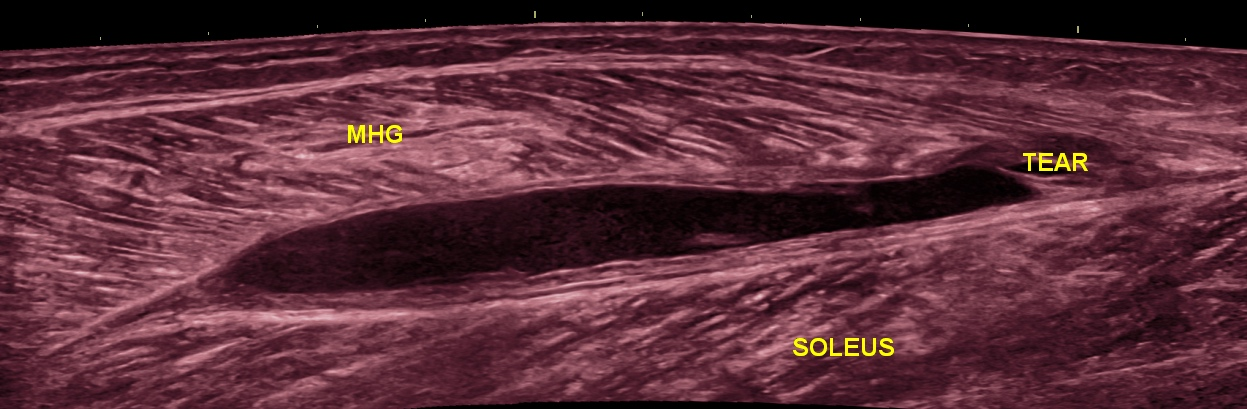

52 yr/M presented with painful calf swelling for 3 weeks. He had experienced a sudden & shooting calf pain during a game of badminton.

Ultrasound (US) imaging shows discontinuity of the medial head of gastrocnemius (MHG) muscle fibers at the distal myoaponeurotic junction resulting in a partial thickness tear. A liquified hematoma is seen tracking between the soleus & medial head of gastrocnemius muscle bellies. The Achilles tendon appears intact.

US imaging is a useful tool in the diagnosis and management of muscle tears & ruling out deep venous thrombosis. It can help to identify the exact site (intramuscular, myo-tendinous junction, myofascial junction) of the muscle tear, length of tear, muscle retraction & presence of an associated hematoma. These factors can predict the athlete’s return to play time.